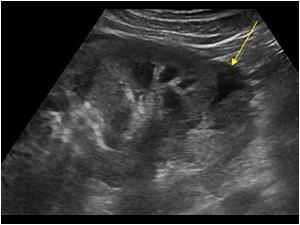

Uraz nerki - USG - co możemy zbadać?

Uraz nerki - TK - co możemy zbadać?

Czy uszkodzony jest miąższ?

Czy występuje krwiak/moczokrwiak?

Czy są uszkodzone drogi moczowe?